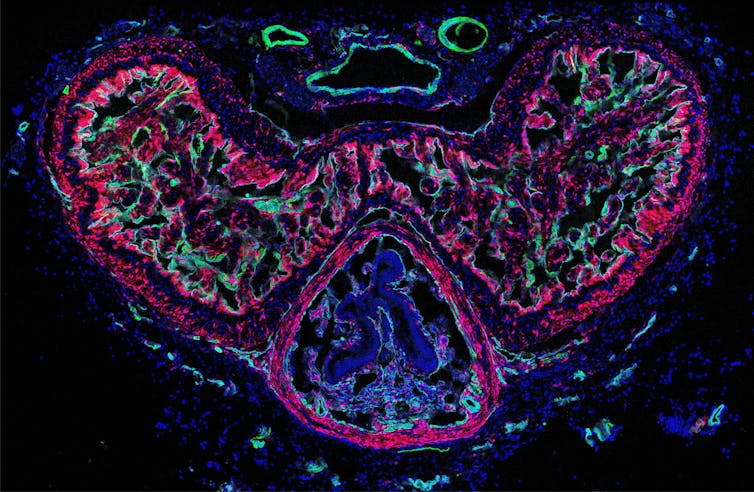

This penis “sponge” is scientifically termed corpora cavernosa. Erections depend on the influx and trapping of blood. Smooth muscle cells regulate the blood flow into the sponge and its subsequent firmness. In a recent study, my colleague and I delved into the role of penile fibroblasts, the most abundant cells in the human penis, about which little was previously known.

We discovered that penile fibroblasts help smooth muscle cells to relax. Using a technique to render cells light-sensitive enabled us to activate fibroblasts by shining blue light from outside onto the penises of mice.